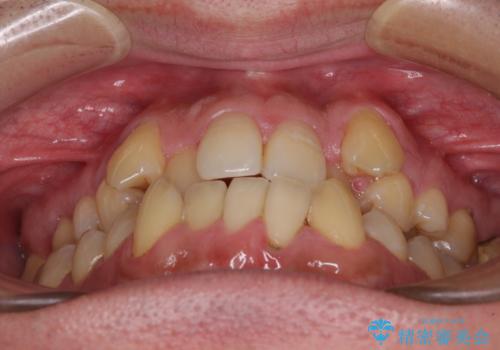

- 八重歯と前歯のクロスバイトを改善したいとのことで来院された患者様です。

デコボコの程度は強かったのですが、口元の突出感はなかったため、非抜歯矯正としました。